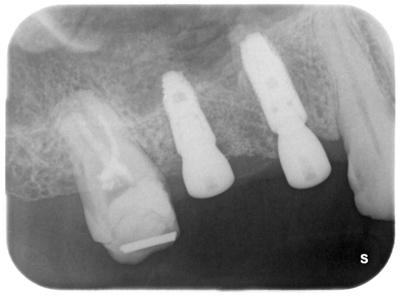

HOME > ブログ 一覧 > インプラント治療 2021.12.13インプラント治療 右上部にサイナスリフト(ソケットリフト)を伴うインプラント治療。 術前。 右上765大きな虫歯、65は歯根破折起こしており保存不可能と判断、抜歯。 使用インプラントはASTRA TX、EV(スゥエーデン) 2次オペ終了時。 年内に765部にプロヴィジョナル装着予定。 この部位以外にも全顎的包括診療行っている。 ここまで治療期間約7ヶ月。 インプラント埋入処置の所要時間は30分程度です。 Recent Entries アライナー矯正(インビザライン、シュアスマイル)費用を2023年 1月から改訂させていただきます(01/09) 本年もよろしくお願いいたします(01/02) 年始の診療について(01/01) 新しいWEBへ移行、年末年始の診療のお知らせ(12/29) ダラダラ根管治療行っても治らないという事(12/21) Category その他の治療(126) インビザライン・矯正(52) インプラント治療(216) ホワイトニング(47) メインテナンス(21) 包括診療(95) 医院からのお知らせ(249) 審美治療(128) 日々雑感(283) 根管治療(100) 歯周病治療(90) 矯正(73) 補綴治療(45) 補綴治療カテゴリを追加(1) 診療全般(44) Archive 2023年1月(3) 2022年12月(6) 2022年11月(14) 2022年10月(6) 2022年9月(8) 2022年8月(7) 2022年7月(13) 2022年6月(8) 2022年5月(7) 2022年4月(7) 2022年3月(6) 2022年2月(7)